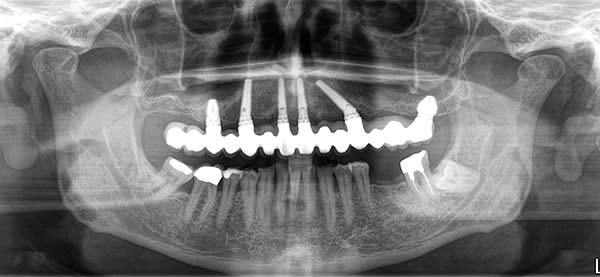

Without exception, all cases should be screw-retained and not cemented. This is made possible through the use of external hexed Co-Axis® implants (Southern Implants, southernimplants.com) with 12°, 24°, and 36° subcrestal angle correction (Figure 1). Screw retention enables retrievability for prosthetic maintenance. Additionally, there is no cement to deal with in the immediate loading environment, and there is no chance for cement-induced peri-implantitis.

Placement of multi-unit abutments at the time of surgery (one abutment/one-time concept)3 is preferable in most multiple-implant cases unless inadequate prosthetic space dictates that the prosthesis connects directly at implant level. Furthermore, with subcrestal angle correction using 12°, 24°, and 36° Co-Axis implants, straight/0° multi-unit abutments can be used in place of cumbersome, prosthetic space-consuming 17° and 30° angled abutments (Figure 2). Multi-unit abutments result in less bone loss and increased comfort for the patient during connection/disconnection of the prosthesis.4